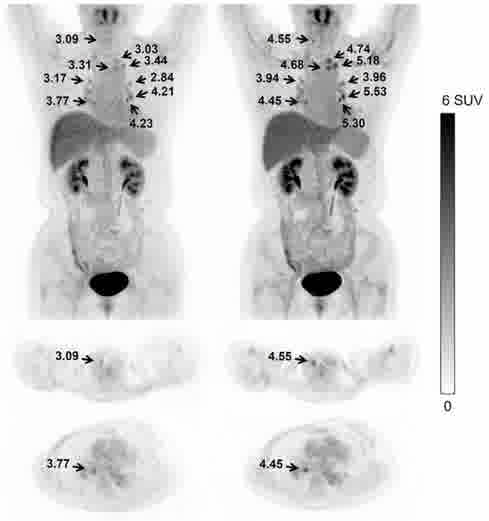

超低计数68Ga三符合重建

采用单事件、低能量事件等全流程数据进行全数字PET图像重建,解决低剂量、多核素等场景下高质量成像问题。

传统算法 改进的算法 双符合重建68Ga和18F混合的信号 三符合重建仅含68Ga的信号 传统算法 改进的算法 缺角度系统